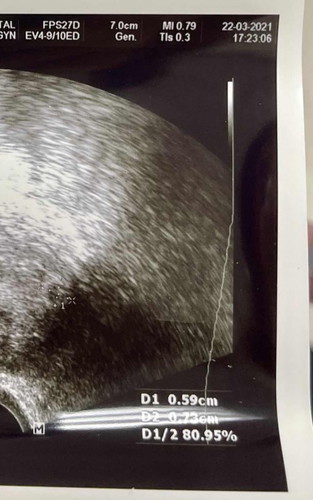

ประจำเดือนวันแรกครั้งสุดท้าย 16 กพ 64 ย้ายตัวอ่อนวันที่ 6 มีนาคม 64 เห็นสองขีดจางๆ วันที่ 10 มีนาคม ค่ะ เห็นถุงตั้งครภ์ 22 มีนาค่ะ